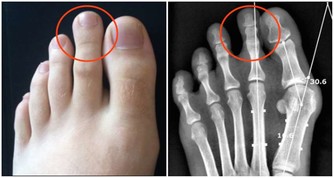

看舌苔,明顯發白,月經量少,顏色黯,有血塊。這都說明體內有寒,是最常見的寒性痛經;像這樣的寒性痛經是最常見的,應該是平時常吃涼東西,冷飲、雪糕、冰激凌、冷麵什麼的;或者,常呆在空調開得很足的環境造成的; 痛經的時候,小肚子冰涼是很常見的,不過,有的人喜按,按一下就舒服多了,這是血虛的表現; 而有的人不敢使勁按,使勁按就很痛,這是血淤的表現; 還有人痛經的時候,小肚子不涼反熱,月經量多、白帶多,那是濕熱型的表現。